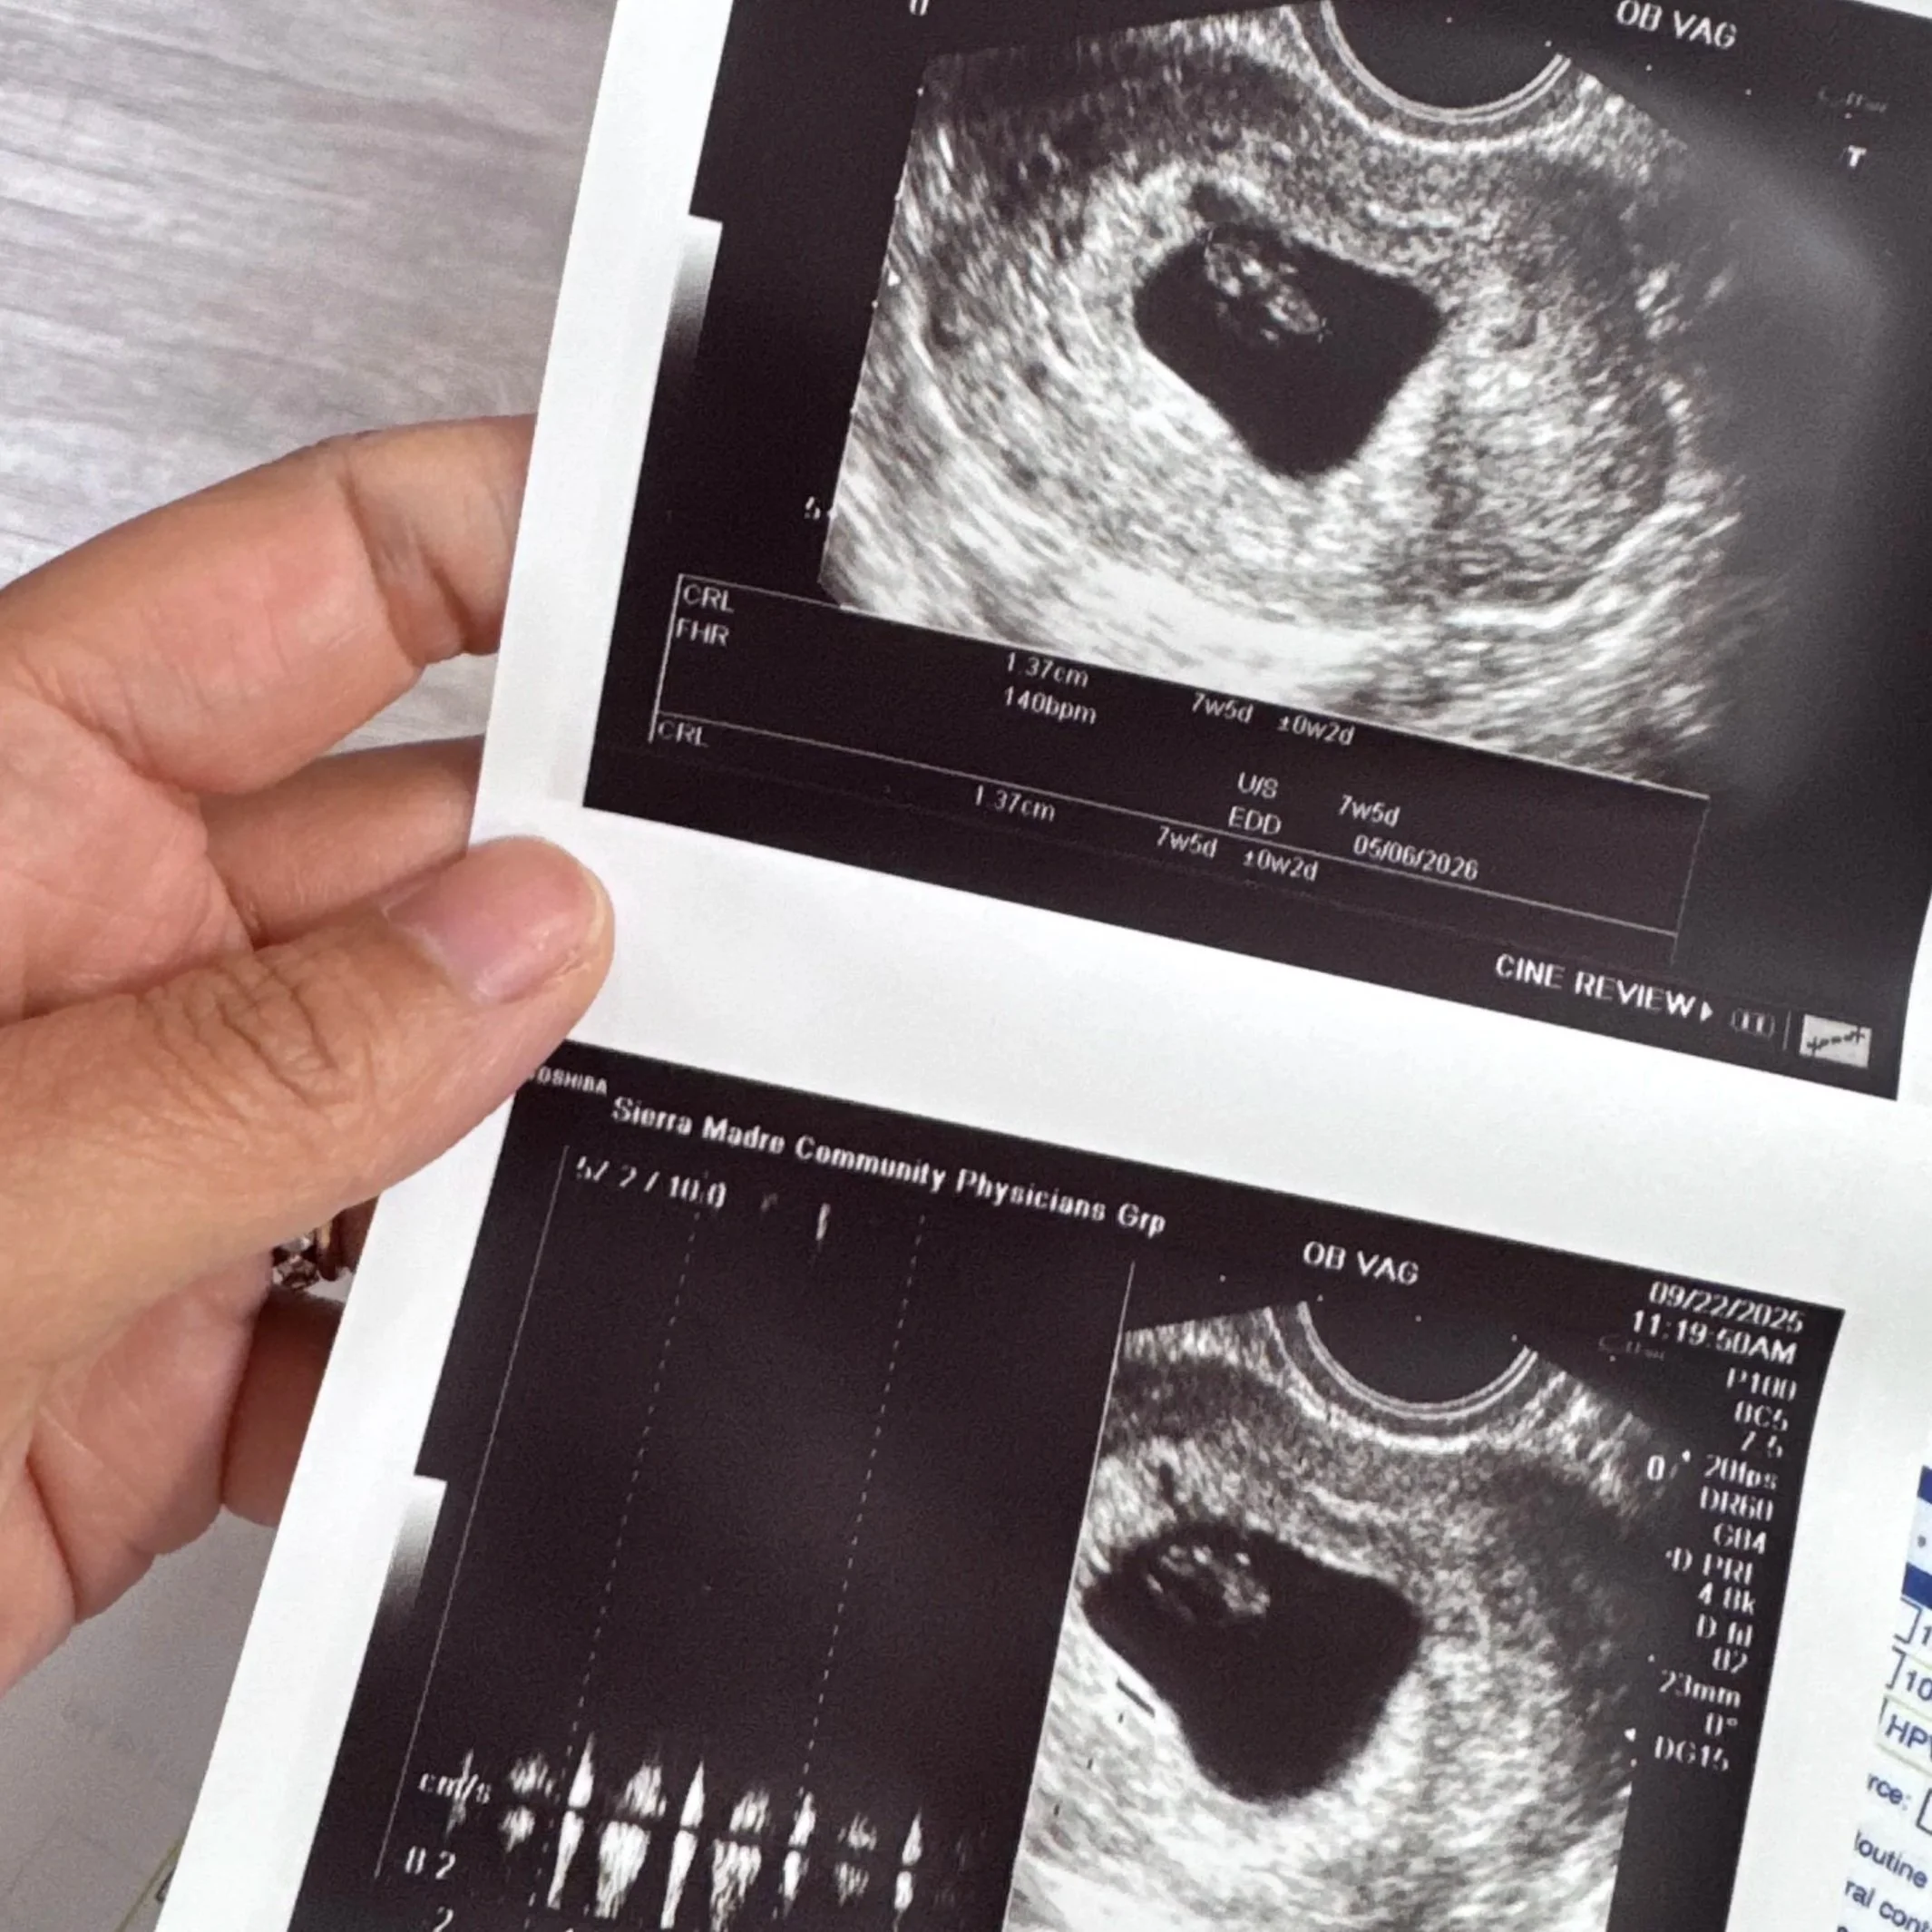

A Surprise Worth Waiting For: Why We’re Not Sharing the Gender of Baby #4

There are a few thoughtful reasons why we’ve chosen not to share the gender of baby #4, and this decision has been rooted in protecting peace, joy, and what feels most meaningful for our family during this season.